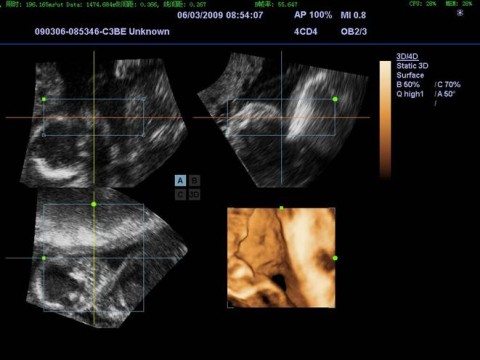

Стационарный УЗИ сканер Mindray DC-7 с цветным, энергетическим, направленным, тканевым, импульсно-волновым и постоянно-волновым доплером и возможностью 4D сканирования.

• 4D (трехмерное сканирование в реальном времени)

• Режим Smart3D™ (технология 3-мерной реконструкции методом свободной руки)

4CD4 Объемный конвексный датчик для получения трехмерного изображения в режиме реального времени (3,2/4,0/4,5/5,0 МГц, вторая гармоника 5,2/5,8/6,4 МГц, радиус 40 мм). Назначение: абдоминальные, акушерские и гинекологические исследования (необходим дополнительный блок 4D).